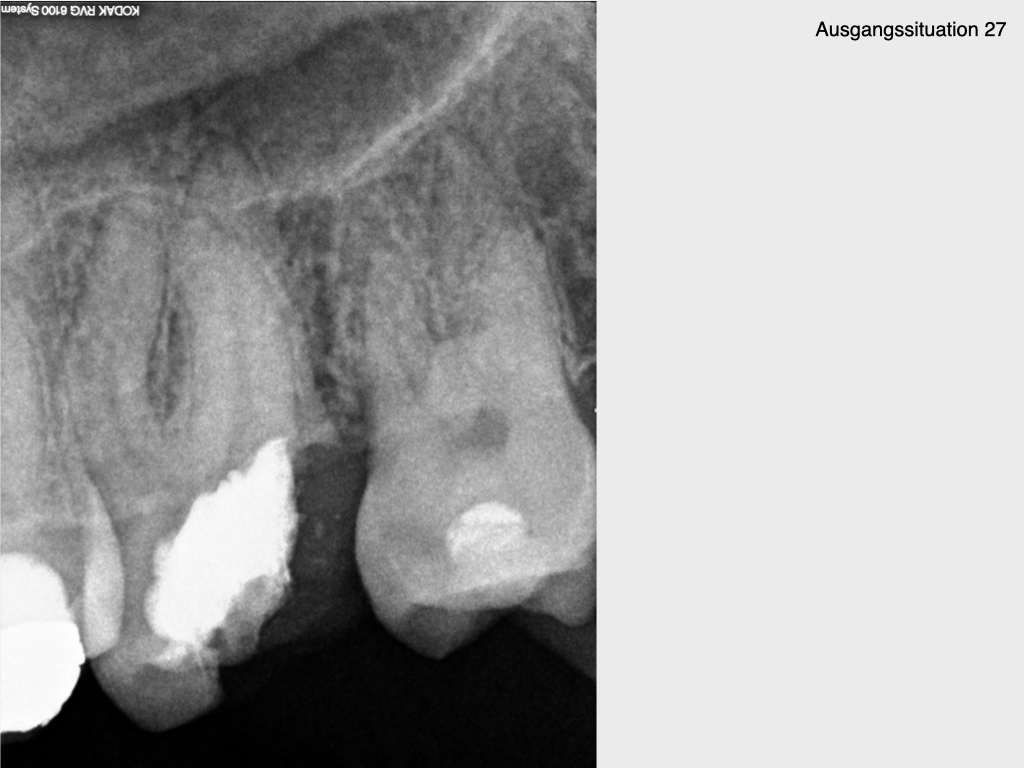

10 Jahres Recall